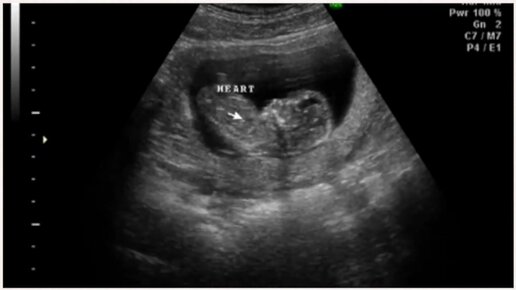

УЗИ на 14 неделе беременности